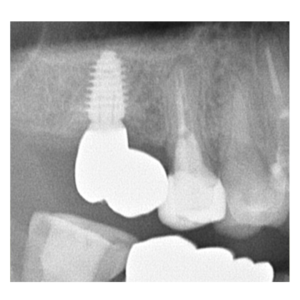

インプラント治療の症例

インプラント治療の症例です。